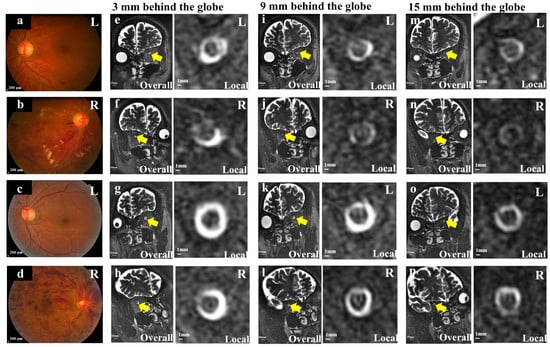

2.3.2. Measurement of the Optic Nerve Sheath and Optic Nerve Diameter, and ONSASW

| ONSASW-3, mm, (mean ± SD) | 1.01 ± 0.21 | 0.99 ± 0.34 | 1.16 ± 0.19 | 1.01 ± 0.16 | 0.763 a | 0.003 b,* | 0.001 d,* | 0.029 d,* |

| ONSASW-9, mm, (mean ± SD) | 0.86 ± 0.15 | 0.82 ± 0.12 | 1.01 ± 0.21 | 0.88 ± 0.14 | 0.103 a | 0.015 b,* | 0.022 d,* | 0.116 c |

| ONSASW-15, mm, (mean ± SD) | 0.79 ± 0.12 | 0.78 ± 0.13 | 0.84 ± 0.10 | 0.81 ± 0.09 | 0.784 a | 0.110 a | 0.063 d | 0.366 c |